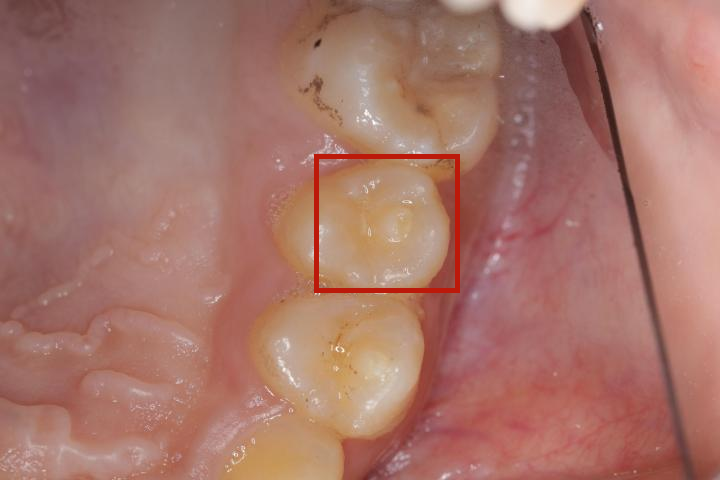

专科检查:全口口腔卫生状况可,少量软垢,25牙合面可见畸形中央尖部分磨损痕迹,松动(I°),叩痛(+),无瘘管,冷诊(- ),根尖区压痛明显。

25牙可见畸形中央尖